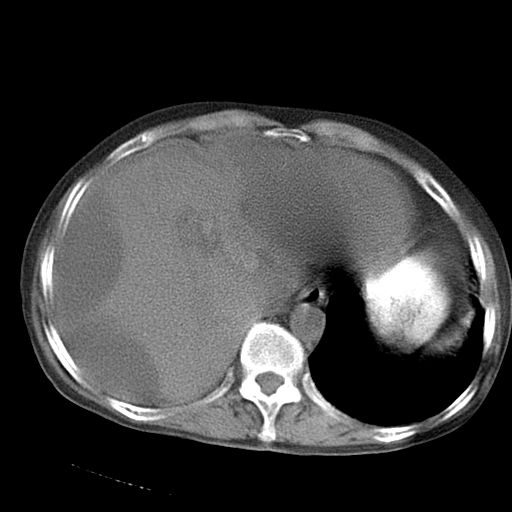

以下是引用dyqct在2006-12-7 21:08:00的发言:[br]考虑:1、肝内外胆管多发性结石伴肝左叶外侧段肝萎缩;[br] 2、右膈下多发脓肿;[br] 3、右侧少量胸腔积液、斜裂积液;[br] 4、左肾囊肿。

以下是引用jiazh在2006-12-7 20:37:00的发言:[br]肝脏周围半狐形低密度影,肝脏表面受压推移,考虑膈下脓肿可能性大;2、右侧胸腔积液

以下是引用拾荒者在2006-12-7 21:44:00的发言:[br]肝内外胆管多发结石,右膈下多发脓肿,右胸膜腔及叶间裂积液,左肾囊肿。[br] [br]